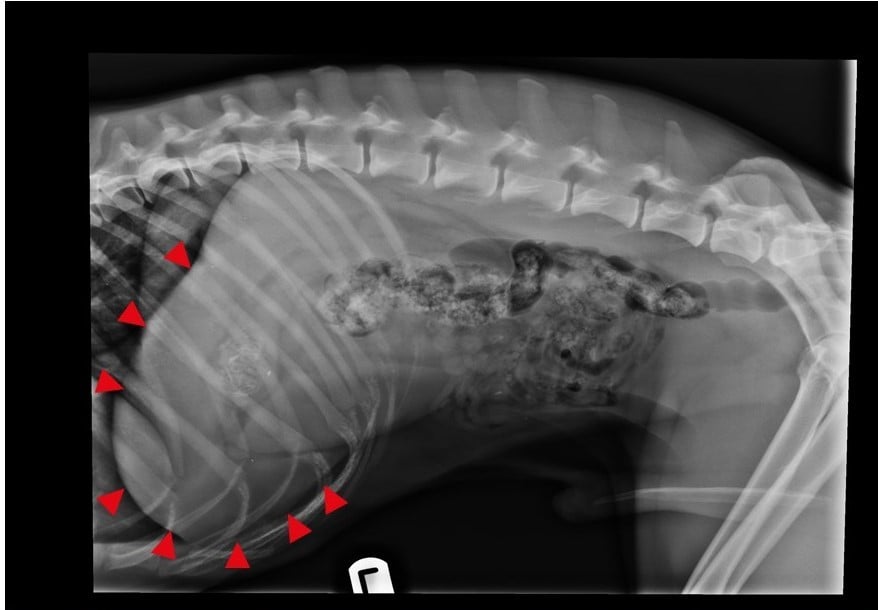

Ultrasonography of the Spleen >>

Ultrasonography of the Liver Part 1 >>

Ultrasonography of the Liver Part 2 >>

Ultrasonography of the Liver Part 3 >>